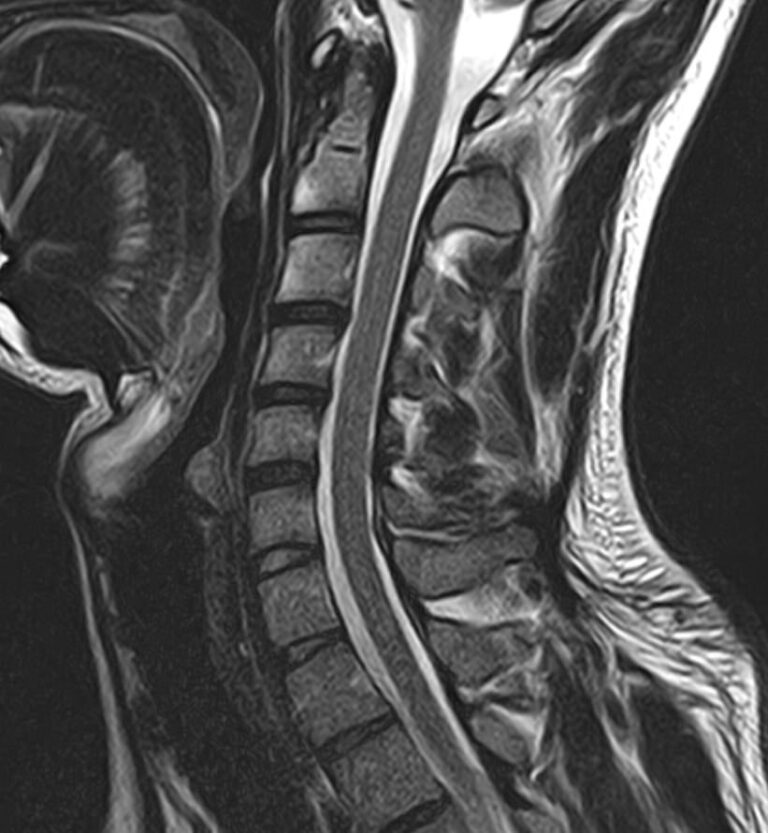

Шейный отдел позвоночника — это самый подвижный сегмент позвоночного столба, который испытывает повышенные нагрузки, подвержен травмам и развитию различных заболеваний. В эту анатомическую область входит 7 верхних позвонков, спинной мозг с отходящими от него нервными корешками, а также проходят крупные сосуды, кровоснабжающие головной мозг. К ним относятся плечеголовной ствол, сонные и позвоночные артерии.

Для того, чтобы оценить состояние шейных позвонков с прилегающими тканями и одновременно визуализировать крупные сосуды шеи, в нашей клинике выполняется комплексное обследование, включающее два протокола: МРТ шейного отдела позвоночника и МР-ангиографию шеи.

В клинике «Доступная медицина» комплексное обследование шейного отдела позвоночника одновременно с МР-ангиографией шеи проводится на новейшем высокопольном томографе экспертного уровня TOSHIBA VANTAGE TITAN 1,5 Тесла, который производит послойное сканирование исследуемой зоны в разных плоскостях, затем при помощи компьютерных программ преобразует полученные данные в трехмерные изображения шейного отдела позвоночника и кровеносной системы, что позволяет проводить точную диагностику и назначать пациенту своевременное лечение.

• дегенеративно-дистрофические заболевания шейного отдела позвоночника (межпозвонковые грыжи, протрузии, остеохондроз, спондилоартроз, спондилез, унковертебральный артроз, сколиоз, усиленный или выпрямленный лордоз как нарушение статической функции позвоночника);

• травмы позвоночника, спинного мозга, связочного аппарата, близлежащих мягких тканей;